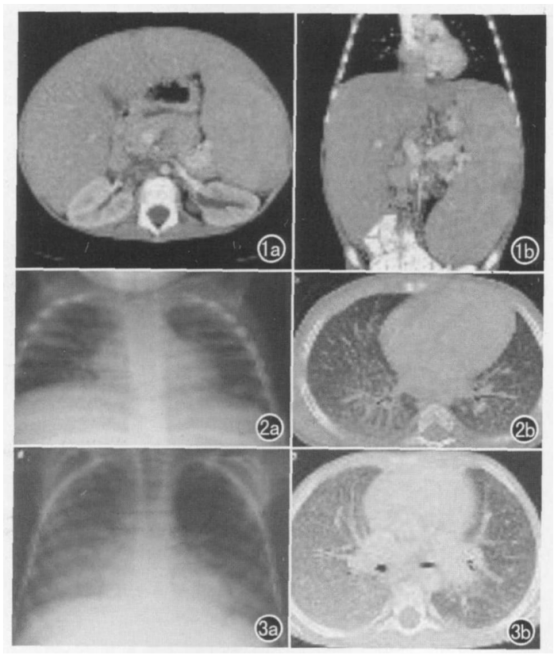

图3 尼曼匹克病B型低剂量MDCT:1a.肾蒂层面轴面扫描;1b.冠状面MPR 均显示明显肝脾肿大巨大脾脏可达小骨盆在侧背旁脾缘处可见楔形梗死区。尼曼匹克病A/B 型(混合型):2a.X线胸片;2b.HRCT 双侧肺网状结节样纹理增多且叶间隔明显增厚。患儿男8岁尼曼匹克病B型:3a.X线胸片;3b.HRCT 大片肺间质性肺部病变尤以右侧为甚伴叶间质增厚和叶间隔增厚以及明显的乳白阴影[5]